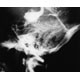

Stereotaktisk bestråling (strålekniv eller gammakniv) gav eliminasjon av cerebrale karmalformasjoner hos 77 % innen tre år etter behandling. Det viser en undersøkelse blant 85 pasienter ved Haukeland Sykehus.

Behandling av arteriovenøse misdannelser i hjernen

Stereotaktisk strålekirurgi av cerebrale arteriovenøse malformasjoner